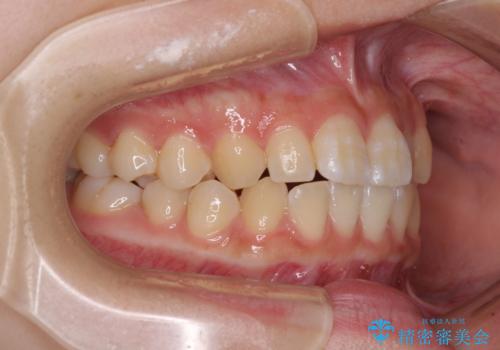

左右ともに上顎第二大臼歯が外側に転位しており、大変磨きにくくなっているため、補助装置により内側に引き込むことで改善することとしました。

外側を向いていた奥歯は比較的早い時期に歯列に収まり、咬み合わせも磨きやすさも改善することができました。

歯列は元々悪くなかったので、1年ほどで治療を終えることができました。